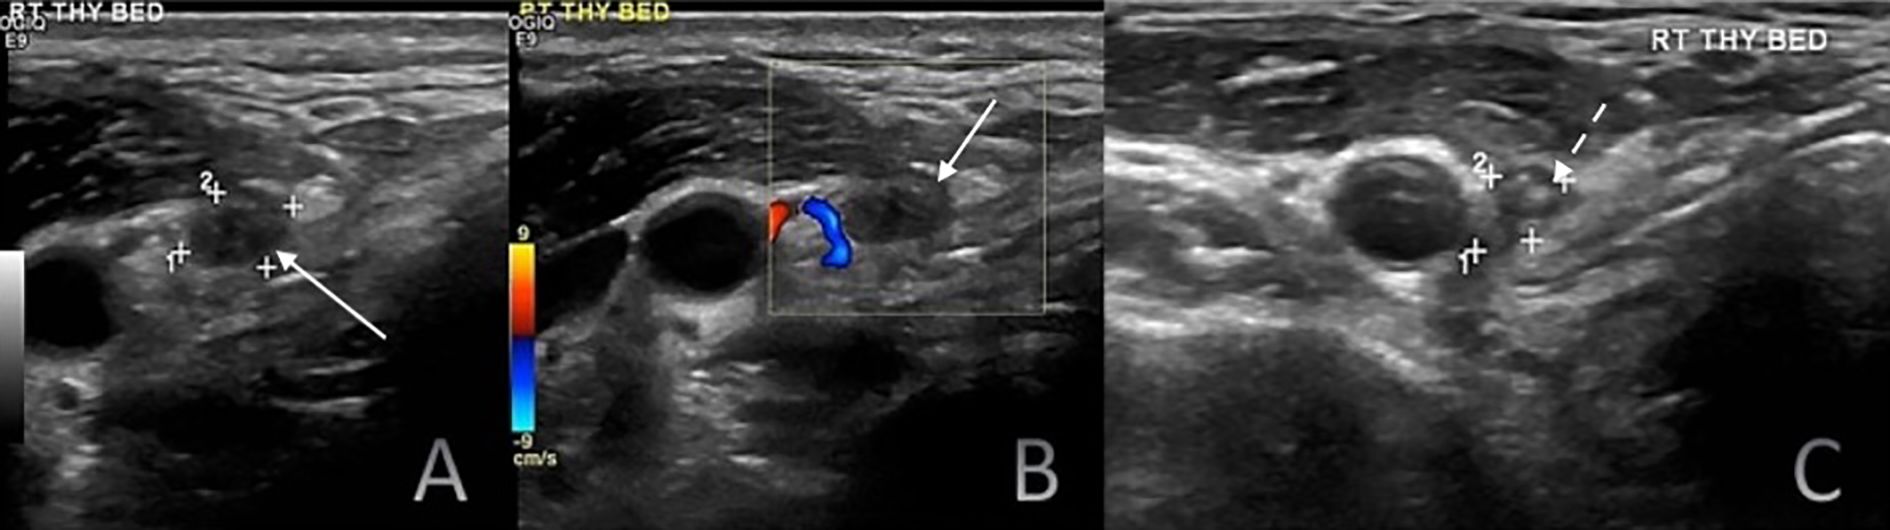

Background: Differentiated thyroid cancer (DTC; including papillary and follicular thyroid cancers) has favourable survival outcomes, with related mortality below 10%. However, 20–30% of patients experience recurrence. Surveillance primarily relies on neck ultrasonography (US) and serum thyroglobulin (Tg) assessment. Purpose: This study evaluated the diagnostic performance of neck US in detecting locoregional recurrence following total thyroidectomy and compared its effectiveness with serum Tg. Materials and Methods: This retrospective, single-centre study analysed 941 DTC patients who underwent total thyroidectomy and neck US between 2009 and 2019. Suspicious US findings were correlated with serum Tg levels and anti-thyroglobulin antibody status. Disease persistence (<6 months) /recurrence (>6 months) was confirmed via fine-needle aspiration cytology/biopsy, iodine scintigraphy, CT, or PET-CT. Patients without US-detected lesions were assessed clinically, biochemically, and via follow-up US. Results: Neck US had a sensitivity of 98.9%, specificity of 63.1%, positive predictive value (PPV) of 50.7%, negative predictive value (NPV) of 99.3%, and an accuracy of 73.01%. Serum Tg (cutoff 1.8 ng/ml derived from receiver operating characteristic analysis) had a sensitivity of 69.2%, specificity of 91.8%, PPV of 61.4%, NPV of 94.1%, and an accuracy of 88.28%. Among 149 patients with US-detected lesions and Tg <1.8 ng/ml, 22 (14.8%) had locoregional recurrence. Five of 43 patients with Tg <0.1 ng/ml had confirmed recurrence. Among lymph nodes ≤6 mm in short-axis diameter with an indistinct fatty hilum, 69.6% were benign. Persistence was detected in 38.5% of patients within six months post-treatment, whereas most true recurrences (61.5%) manifested after six months. Conclusion: Neck US is highly sensitive but moderately specific for detecting locoregional recurrence post-thyroidectomy, complementing Tg. Study limitations include its retrospective design, single-centre setting, and lack of inter-observer variability assessment. A risk-adapted multimodal surveillance strategy with 6-monthly US for two years is recommended.